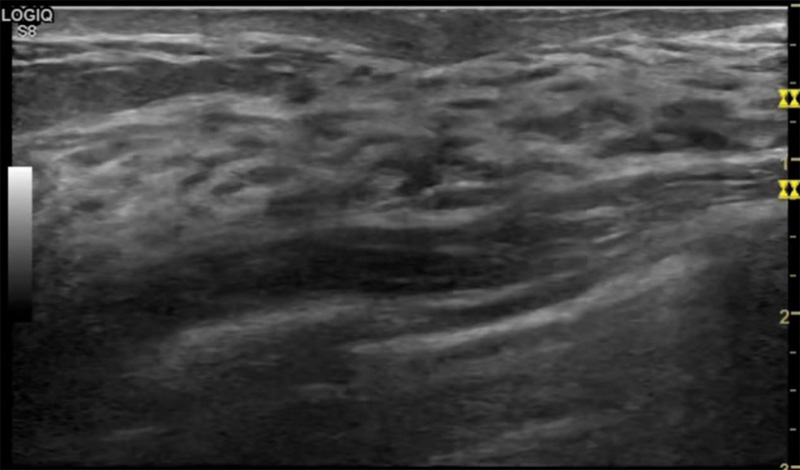

乳房脹痛,觸摸疼痛,手摸起來感覺有腫塊。這個是什麽問題呢?醫生診斷一般是乳腺增生。那麽在乳腺秋葵视频APP下载安装檢查後,報告單卻顯示雙乳未見明顯占位性病變。乳腺增生是很多女性,特別是育齡期女性都有的經曆、到底乳腺增生症狀有哪些?會給秋葵视频男人的加油站帶來怎樣的影響呢?乳腺增生不是腫瘤跟炎症。乳腺組織增生及退行性變跟內分泌功能紊亂有關係。正常的生理改變。還有乳腺病,良性乳腺結構不良等名稱。

乳腺增生有什麽症狀,病因?比較典型的就是乳房疼痛,特別是經前症狀比較重,經後就有所緩解。有時候還能碰到乳房硬塊。根據經期的變化而變化硬度大小都有變。乳腺在內分泌激素,伴隨月經周期有增生問題。內分泌激素代謝失衡,雌激素水平增高,出現乳腺組織增生過度,增生組織不退的情況下,就會有乳腺增生症狀。這個不會增加乳腺癌的風險。所以不用緊張的。不過乳腺癌的病人都會有乳腺增生。所以乳腺增長有沒症狀,都需要進行常規的體檢。

乳腺秋葵视频APP下载安装便捷安全的檢查方法,國際上有乳腺檢查超聲的指南。可以針對乳腺疾病做出係統的分類。《乳腺超聲若幹臨床常見問題專家共識(2018版)》說明不建議提示乳腺增生症。單純的囊腫,乳腺改變等。在BI-RADS分類中已經納入不同類別。針對未發現占位的乳腺,雙乳未見占位性病變(BI-RADS 1類)。因此看到這樣的檢查報告時候,不用緊張擔心,占位性結節沒有形成。